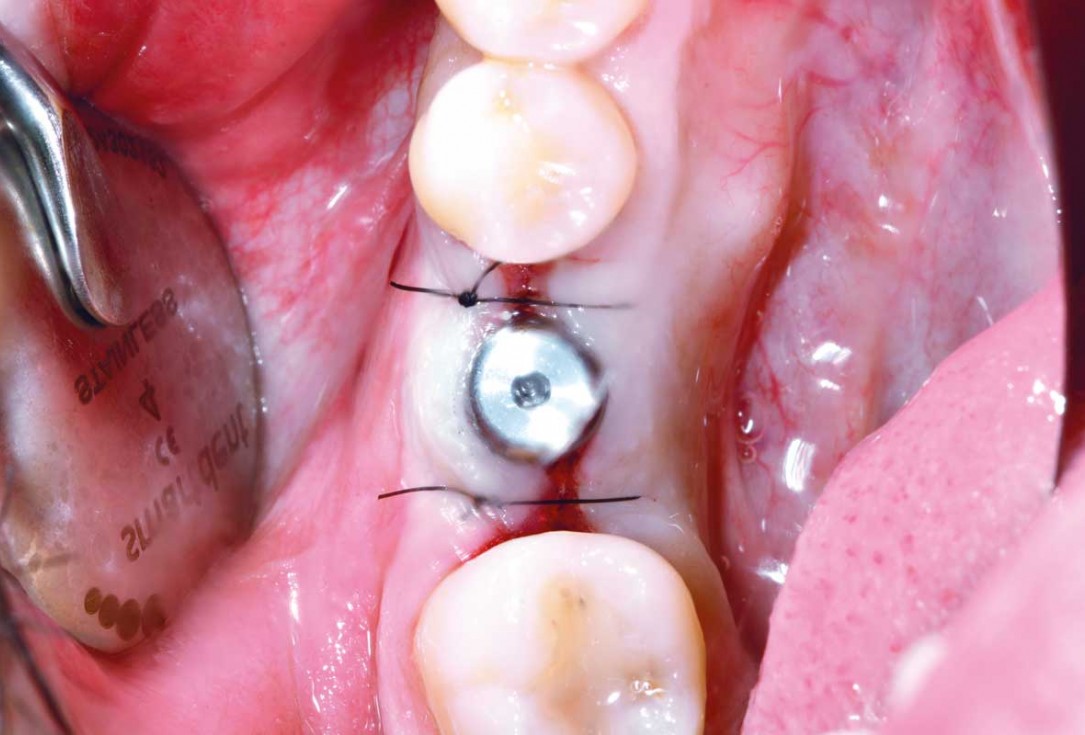

18/25 - Insertion of the healing cap and suturingImmediate implant placement and peri-implant bone augmentation with cerabone® plus - Dr. R. Block Veras